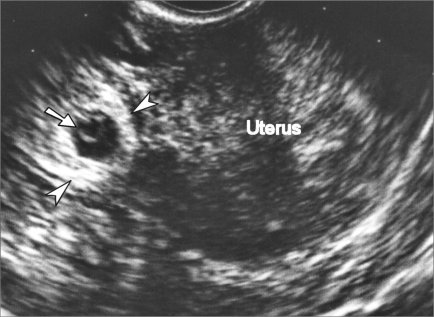

• Pelvic ultrasound

• elevated b-hCG with no signs of uterine gestational sac by ultrasound is highly suspicious

• if symptoms are present an adnexal mass can usually be seen with transvaginal ultrasound